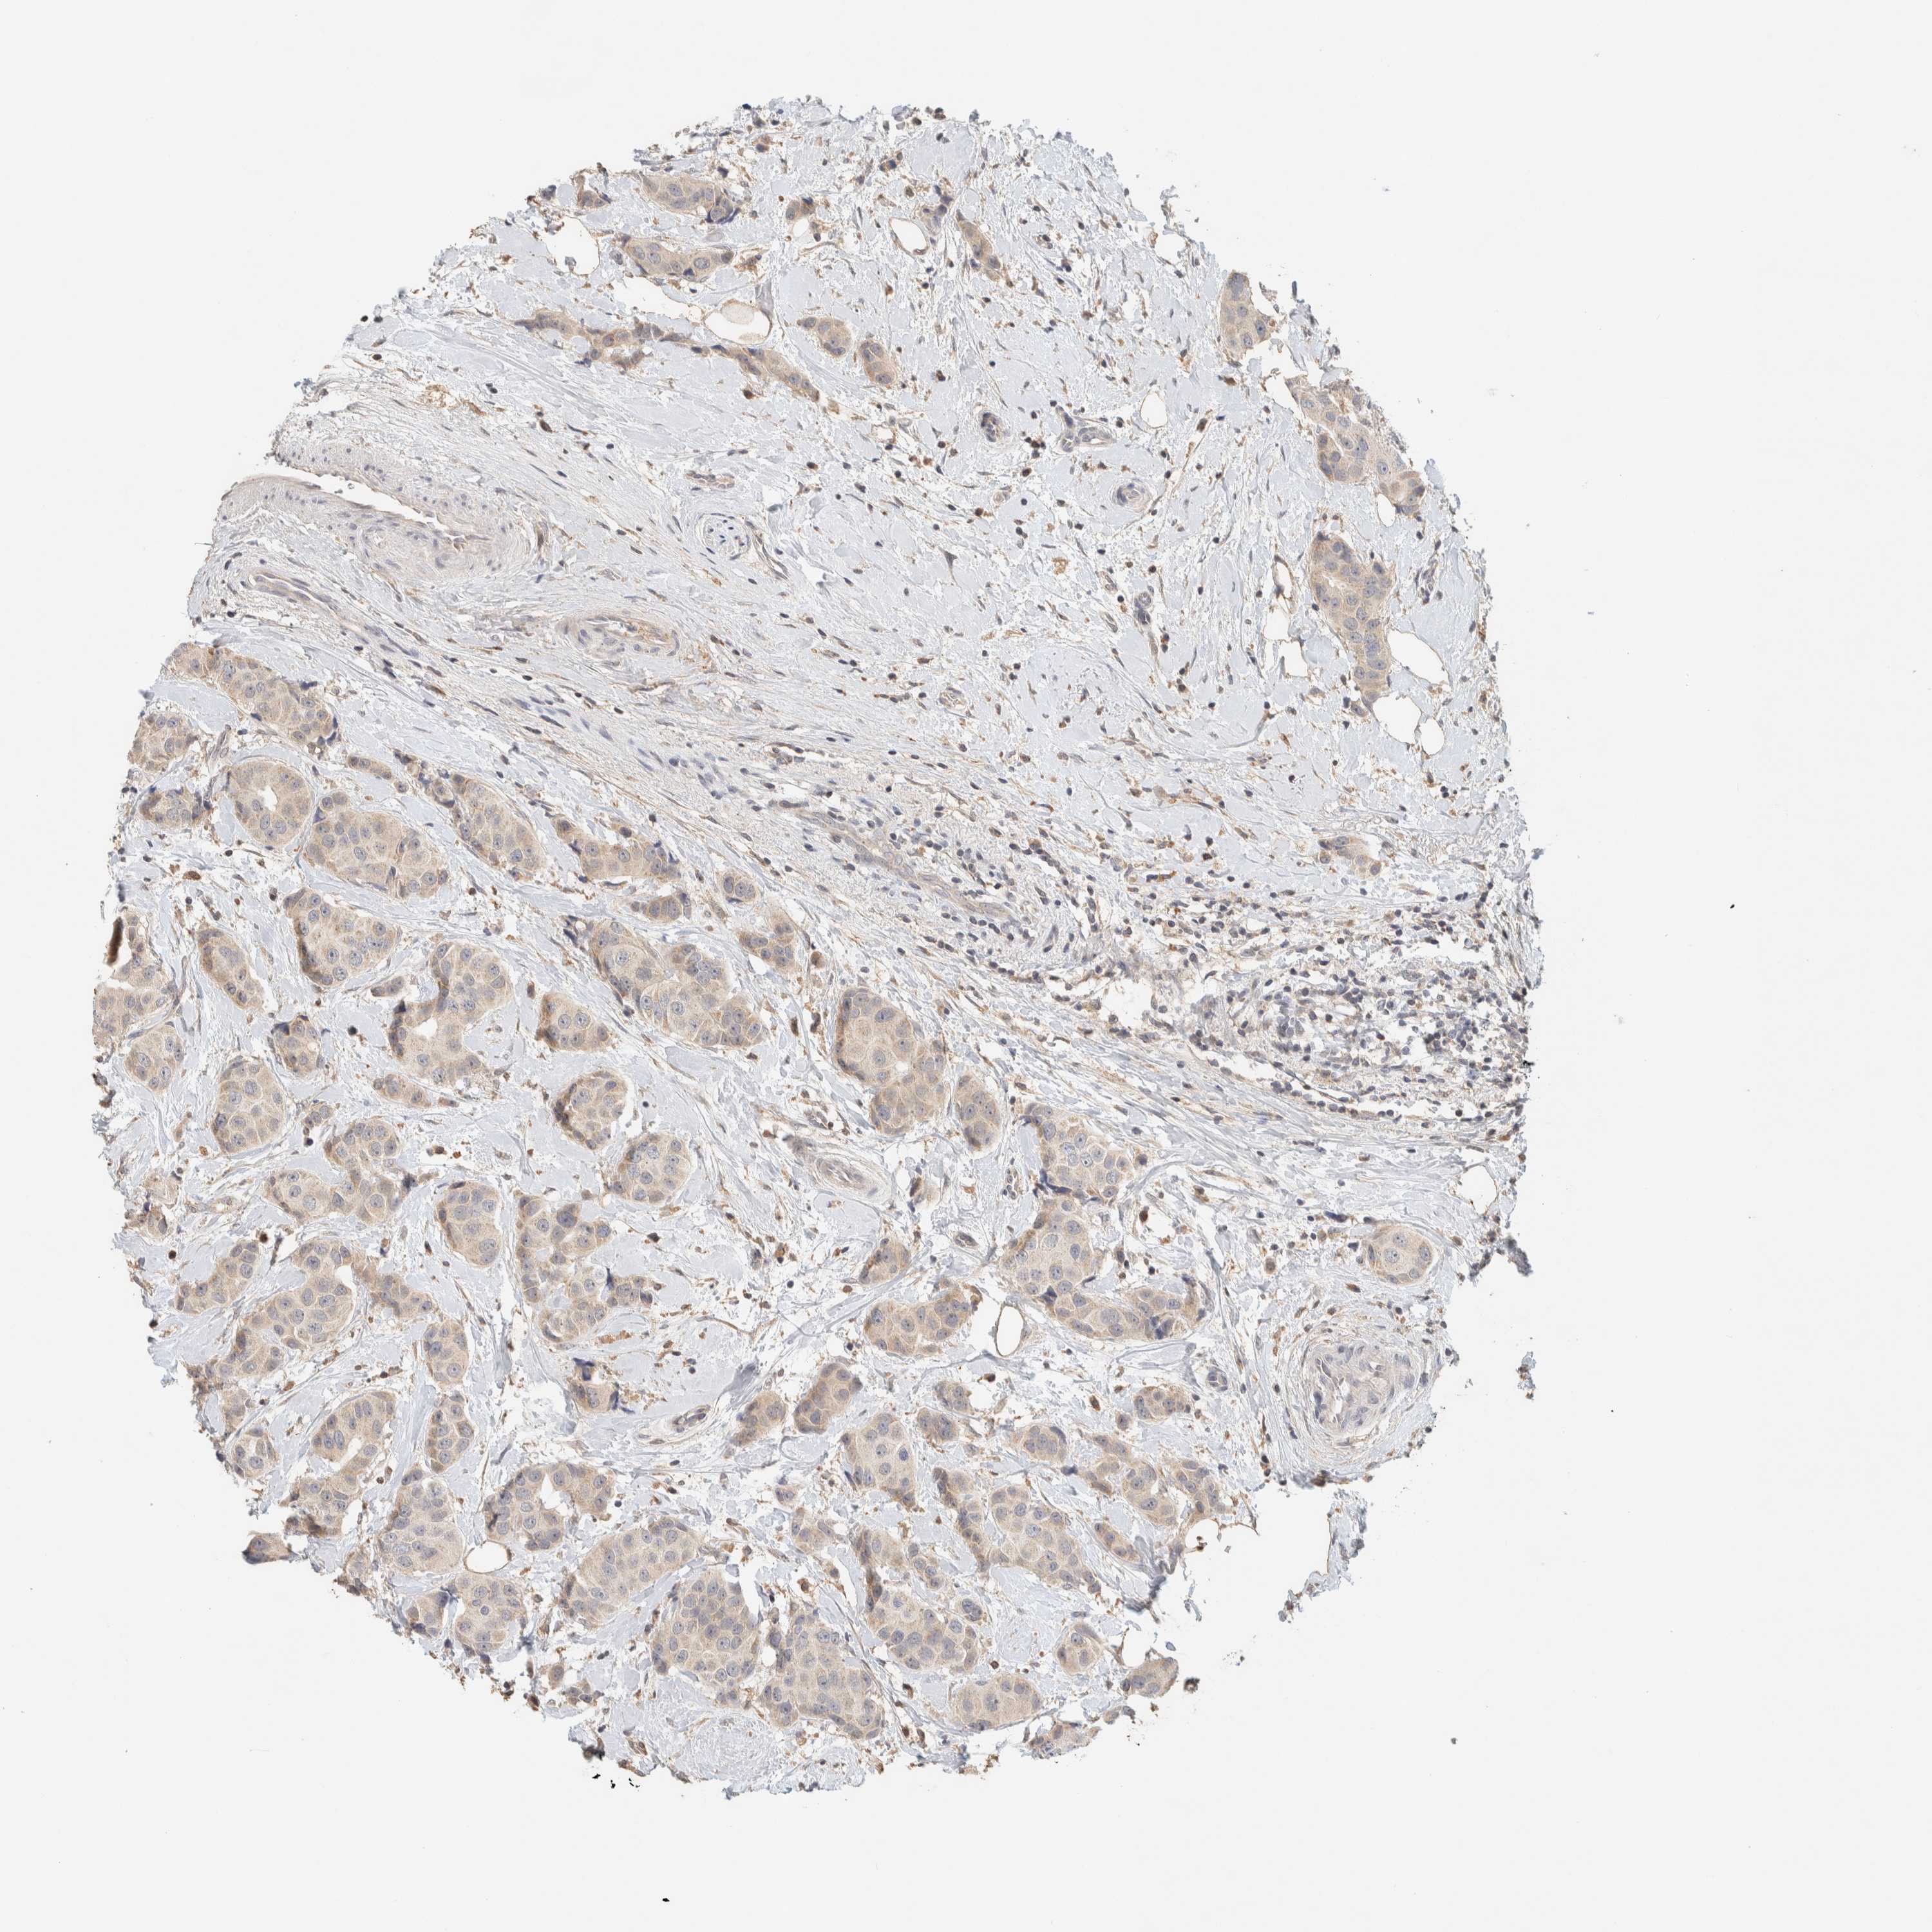

CANCER BREAST CANCER Show tissue menu

BRCA TCGA BRCA VALIDATION PROTEIN EXPRESSION

ANTIBODIES

AND

VALIDATION